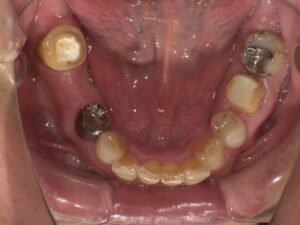

術前・術後写真

【術前】

右下7番の状態が悪い患者さんでした。骨吸収を起こしており動揺もでていたので、抜歯も考えましたが、インプラントを選択されたので、骨吸収像は見られますが、動揺はほぼ無くなり噛めている状態を維持されています。インプラントは他の歯を守ることができる治療法だと思えた症例となりました。